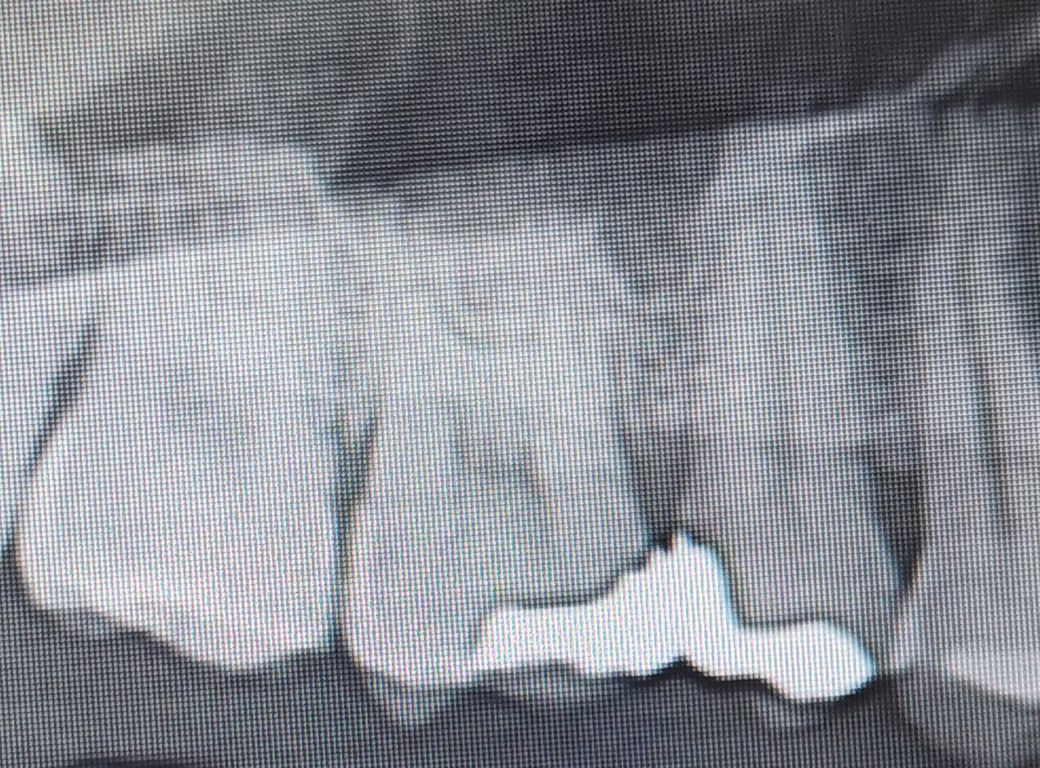

위쪽 치아 인레이(세라믹) 접합부가 너무 빡빡한 느낌이 듭니다.

인레이 한 치아가 너무 빡빡한 느낌이 듭니다.

치실도 힘겹게힘겹게 들어가고..

아래부분과 교합도 안맞는거같습니다.

• 1번 째 사진